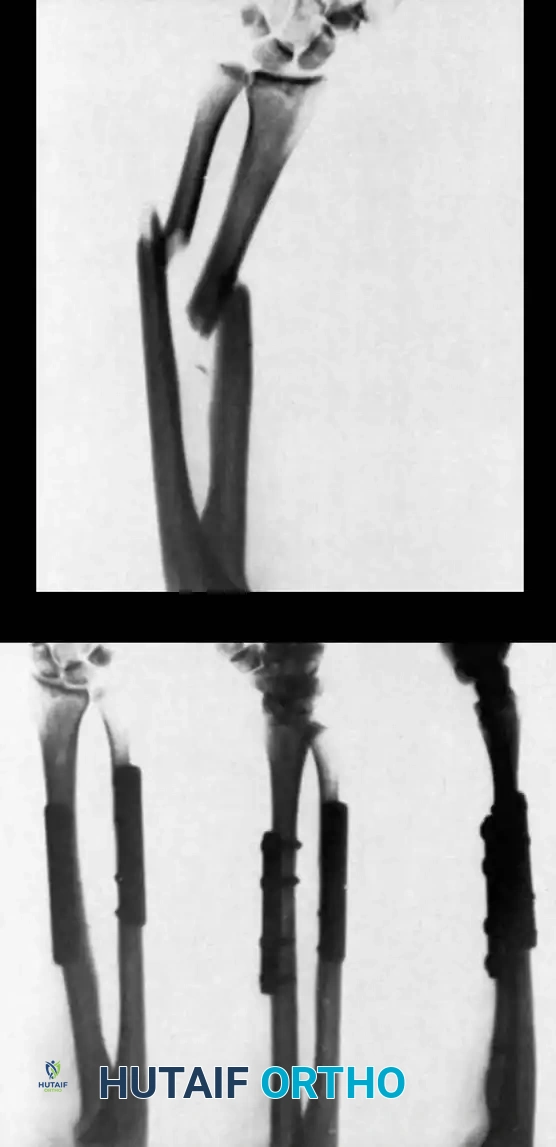

2. Intramedullary Fixation with Tension Band

If the fracture is more distal, or if there is a tendency for the proximal fragment to angulate posteriorly, a simple tension band wire is insufficiently stable. In these cases, intramedullary fixation (using Kirschner wires or a large cancellous screw) is combined with the tension band.

Kirschner Wires vs. Cancellous Screws:

* K-wires: The AO technique utilizes two parallel K-wires (1.6 mm or 2.0 mm) driven down the medullary canal. To prevent proximal migration, the K-wires must engage the anterior cortex of the ulna distal to the coronoid.

* Cancellous Screw: A biomechanical analysis by Murphy et al. demonstrated that a long 6.5-mm or 7.3-mm AO cancellous screw combined with a figure-of-eight wire provides a significantly stronger construct than K-wires. The screw must be long enough to achieve secure purchase in the ulnar diaphysis.

Fig. 54-55 Olecranon fracture repaired with long 6.5-mm AO cancellous screw and figure-of-eight tension band wire loop. Screw must engage cortex of diaphysis of ulna.

🔪 Surgical Technique: K-Wire and Tension Band (AO Technique)

- Reduction: Anatomically reduce the fragments and hold them temporarily with a reduction clamp.

- K-Wire Insertion: Introduce two parallel K-wires longitudinally from the tip of the olecranon across the fracture site. Direct them slightly anteriorly so they engage the anterior ulnar cortex distal to the coronoid process.

- Wire Loop: Pass an 18-gauge wire through a transverse drill hole in the distal fragment. Cross the wire in a figure-of-eight fashion over the posterior surface.

- Proximal Capture: Pass the wire around the protruding proximal ends of the K-wires.

- Double Twist: Weber and Vasey suggest twisting both limbs of the figure-of-eight loop. This double-twist modification ensures uniform compression across the fracture site.

- Securing K-wires: Bend the proximal ends of the K-wires 180 degrees, cut them short, and tap the bent ends deep into the triceps insertion and proximal bone to prevent symptomatic hardware prominence and migration.

Fig. 54-56 A and B, Transverse olecranon fracture repaired with Kirschner wires and tension band technique. C, Double twist modification of wiring suggested by Weber and Vasey.